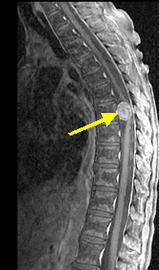

A: MRI (thoracic) With And Without Contrast

mri contrast without thoracic lumen neurology luc curriculum meded radio edu

Learning Radiology - Discitis

discitis spine lumbar normal osteomyelitis disc radiology destruction disk endplates there narrowing learningradiology